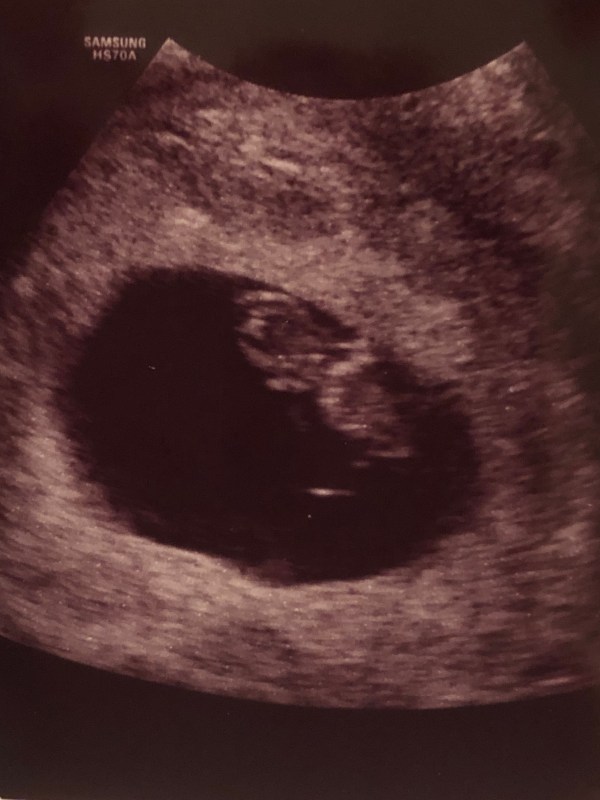

On January 3rd, we saw our baby for the first time…

And ever since then, we just keep reminding ourselves of Faith over Fear. We saw baby C again on Adam’s birthday, growing so much already. (Have you ever seen a cuter nose??)